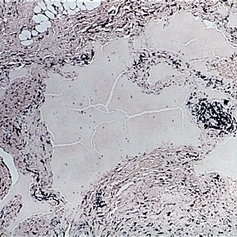

Microphthalmos with cyst. Left side shows the macroscopic appearance and right side the microscopic appearance, of a microphthalmic eye with continuou cyst. The eye has multiple anomalies such as hypoplasia of the iris, cataract, nonattachment of the retina, and retinal dysplasia (right, H&E x 1).

Condition/keywords: cataract, cyst, dysplasia, hypoplasia, microphthalmos